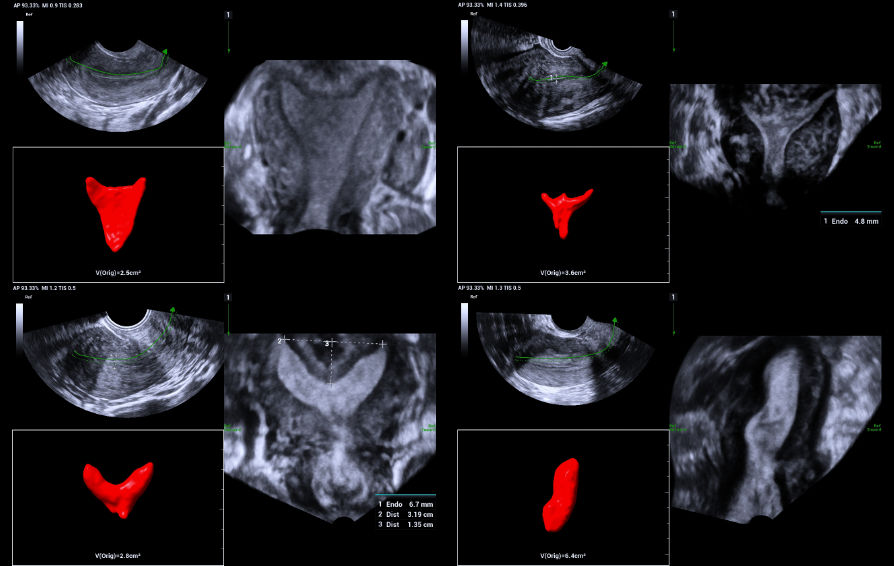

2. Arcuate uterus.

Use of Smart ERA in diagnosis of Mullerian duct abnormalities - Arcuate uterus

Smooth indentation of fundal endometrial canal, the depth of indentation is <1 cm.

4. Subseptate uterus.

Use of Smart ERA in diagnosis of Mullerian duct abnormalities - Subseptate uterus

The fundal indentation was an acute angle at the central point > 1.5 cm deep. Using iPage+ clearly illustrates the extent of fundal indentation and the single cervix and vagina.

5. Sub-mucosal fibroid indenting the fundal endometrium.

Use of Smart ERA in diagnosis of Mullerian duct abnormalities - Sub-mucosal fibroid indenting the fundal endometrium

Smooth indentation of fundal endometrium giving a similar appearance to arcuate uterus.